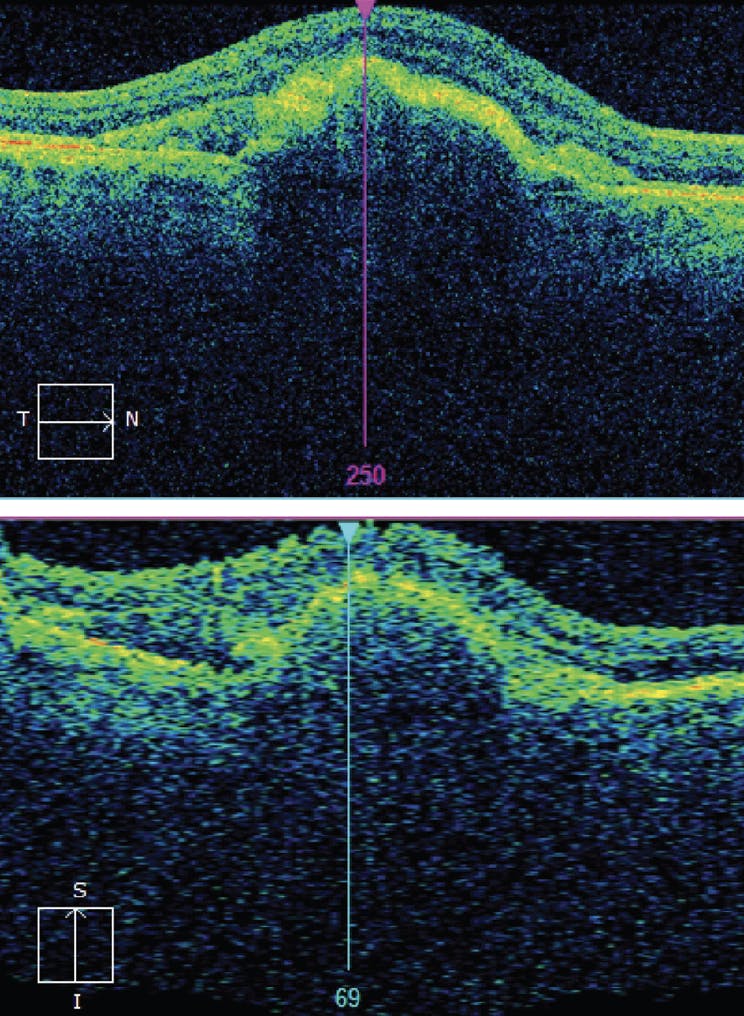

In July 2021, the system alerted my office to changes to the patient’s left eye testing. The patient was called and scheduled for an immediate appointment. On examination, his VA was 20/30 OS. The anterior segment examination was unremarkable, while dilated fundus examination of the left eye showed subretinal fluid and new choroidal neovascularization (CNV). Based on this, the patient was diagnosed with conversion to wet AMD with CNV in the left eye (Figure 3). The patient received anti-VEGF injection on the initial visit and continued monthly injections. Currently, he is extended to receive treatment every 8 weeks with VA improved to 20/25 OS and resolution of CNV (Figure 4).

<p>Figure 3. Changes in the at-home testing prompted an immediate in-office visit, which revealed new choroidal neovascularization and conversion to wet AMD.</p>

Figure 3. Changes in the at-home testing prompted an immediate in-office visit, which revealed new choroidal neovascularization and conversion to wet AMD.

<p>Figure 4. Intravitreal anti-VEGF injections improved the patient’s VA to 20/25 OS and led to the resolution of the choroidal neovascularization.</p>

Figure 4. Intravitreal anti-VEGF injections improved the patient’s VA to 20/25 OS and led to the resolution of the choroidal neovascularization.